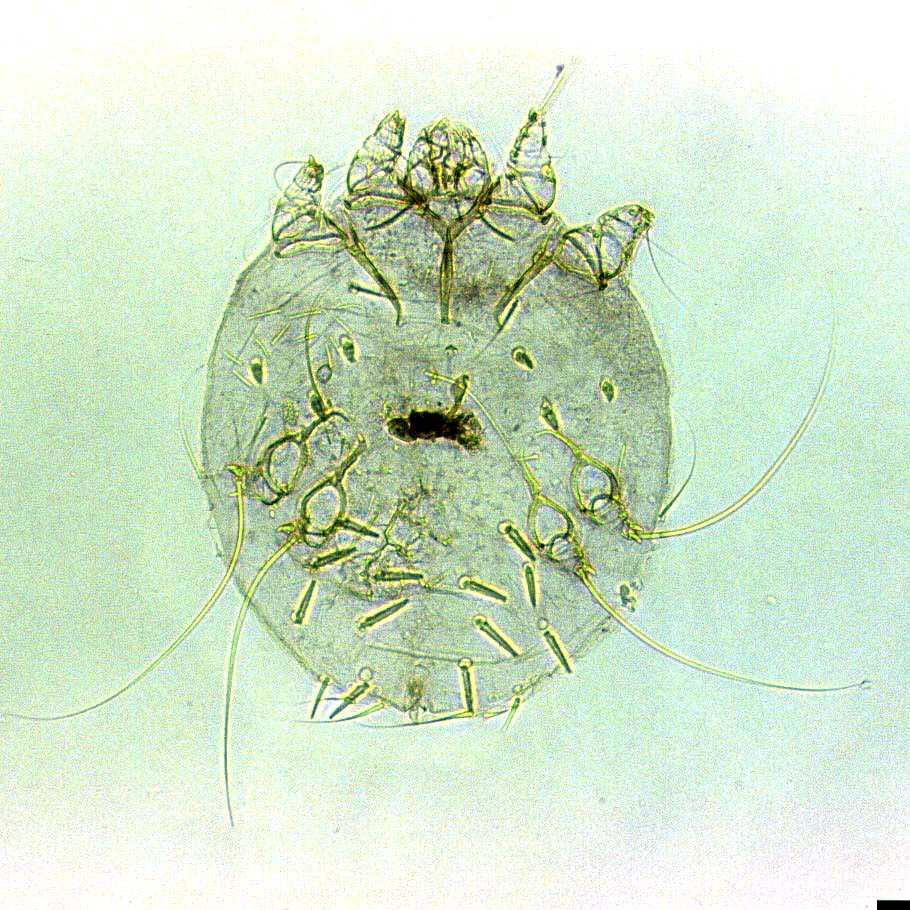

На фото собака поражена саркоптозом.

Все возбудители саркоптоза имеют одинаковый цикл развития и сходное внешнее строение. При изучении фото клещей, паразитирующих на животных, обнаруживается их поразительное сходство с чесоточным зуднем человека. Оно объясняется одинаковым образом жизни и принадлежностью к одному роду.

Размер паразита не превышает 0,35 мм, самцы меньше самок. Ротовой аппарат грызущего типа. Действуя им, клещ отрывает кусочки эпидермиса, проделывая туннели. Удерживаться в своих ходах и на поверхности кожи паразиту помогают расположенные на задних лапках упругие щетинки, снабженные присосками.

Паразит передвигается в эпидермисе со скоростью несколько мм в сутки, на поверхности кожи развивает скорость до 3 см в минуту.

Самки откладывают яйца в ходах. Личинки поселяются выше, под чешуйками эпидермиса. Там они проходят несколько стадий развития. Достигнув зрелости, личинки спариваются на поверхности кожи и начинают прогрызать ходы.

Каждая самка живет 1-1,5 месяца. Полный цикл развития «от яйца до яйца» занимает 8-20 дней.